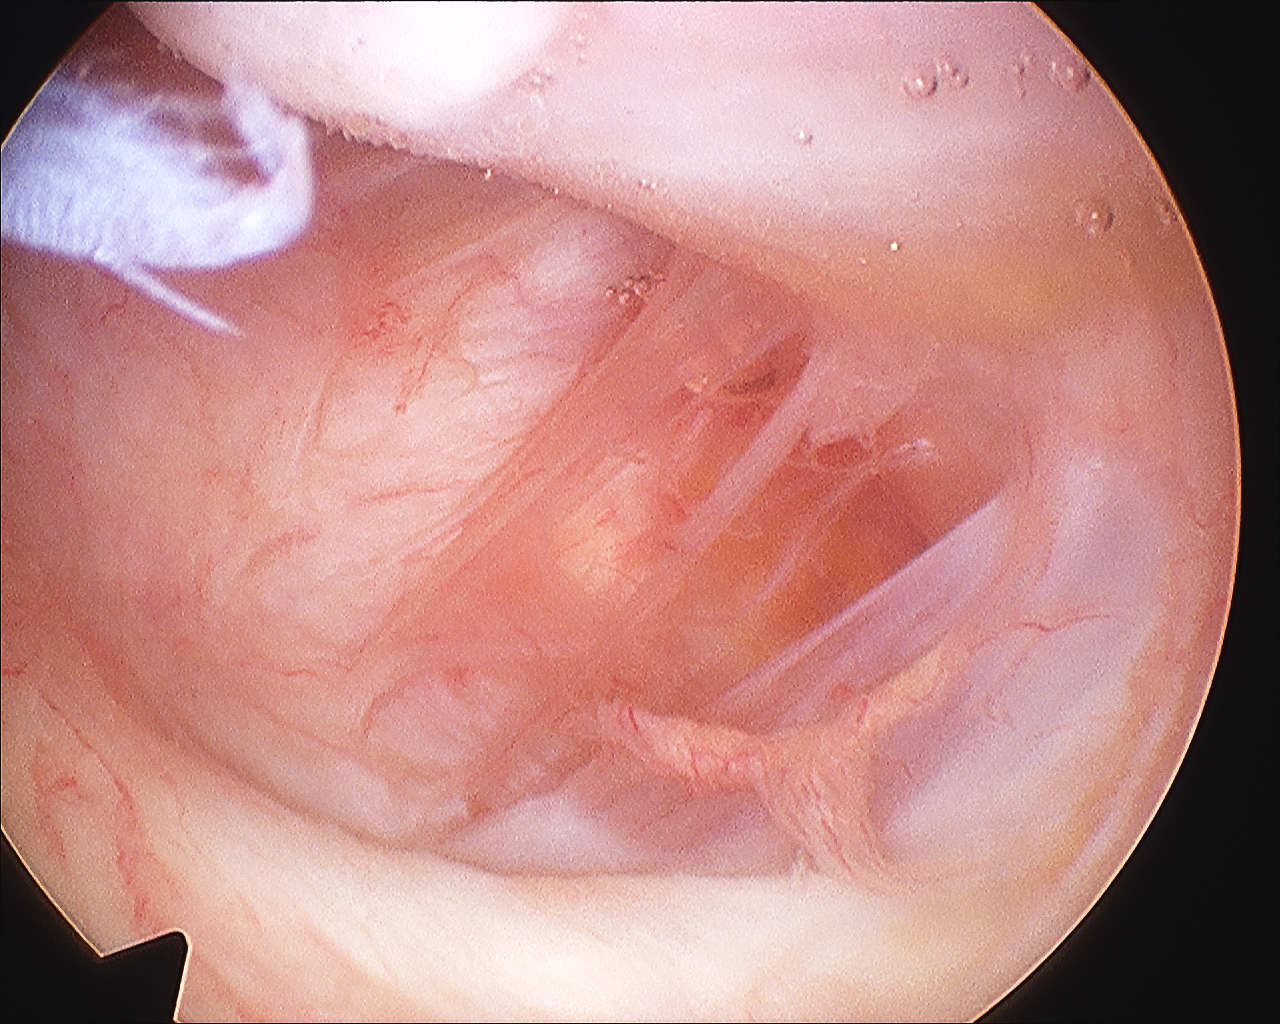

HAGL

Definition

Humeral Avulsion of Glenohumeral Ligament